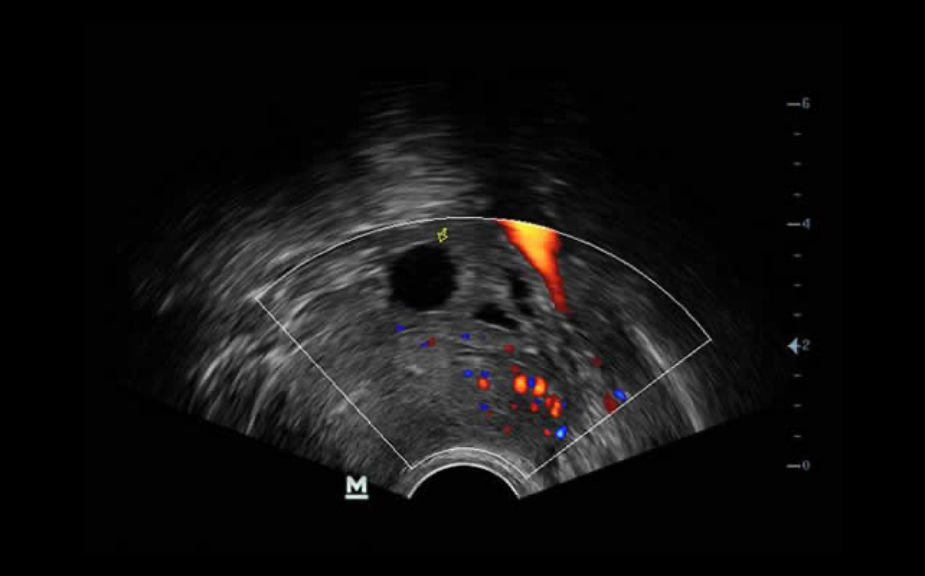

PSH? (Phase Shift Harmonic Imaging)

ImĂĄgenes de armĂłnicos purificados con desplazamiento de fase para una mejor resoluciĂłn de contrastes que proporciona imĂĄgenes mĂĄs nĂtidas con excelente resoluciĂłn y menos ruido.

iBeam?

Permite el uso de varios ĂĄngulos de exploraciĂłn para formar una sola imagen, lo que ofrece una mayor resoluciĂłn de contrastes y una mejor visualizaciĂłn.